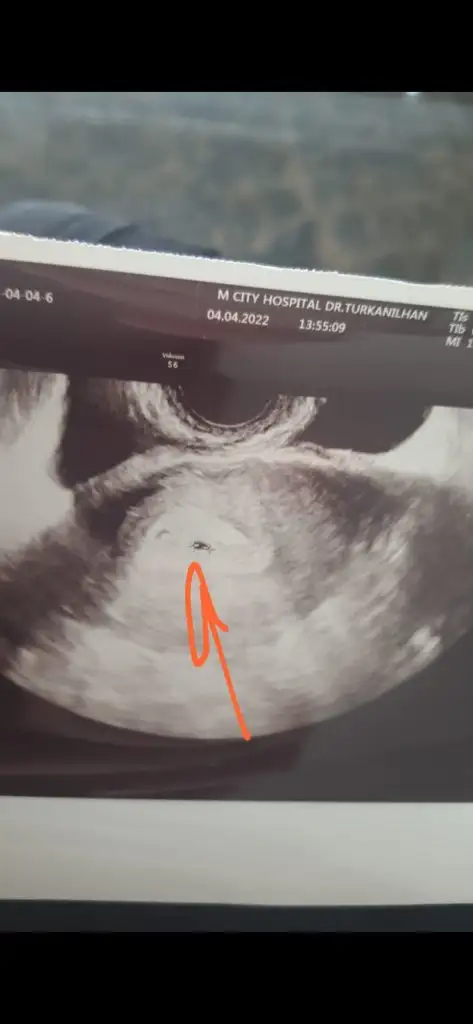

Buda 16+5 ama bacak arasından resim yok maalesef